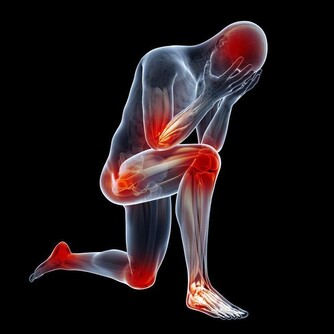

關節病是可以困擾老中青三代的常見的骨科疾病,其中,膝關節作為身體重要的支撐及活動結構,

因運動不當或隨著年紀變大,膝關節出現損傷的機率往往較其他關節更大。

組成膝關節的小夥伴有骨頭、軟骨、肌肉、韌帶和肌腱,構成膝關節的任何一個成分出了問題,都壞導致膝關節疼痛或不能行動。

不分種族不分性別不分年齡,任何人都可能患上關節病。 關節病可以是膝關節直接受到衝擊或扭傷,也可以是關節骨和軟骨部分磨損、撕裂而引起。 炎症性關節病還可以由風濕性疾病引起,比如風濕性關節炎或系統性紅斑狼瘡,這些疾病導致的關節腫脹對關節的損傷是永久性的。